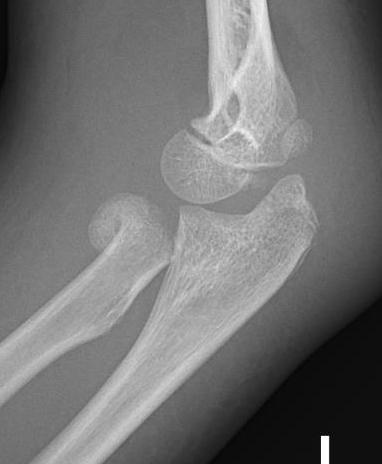

Xray

Displaced and angulated radial neck fracture